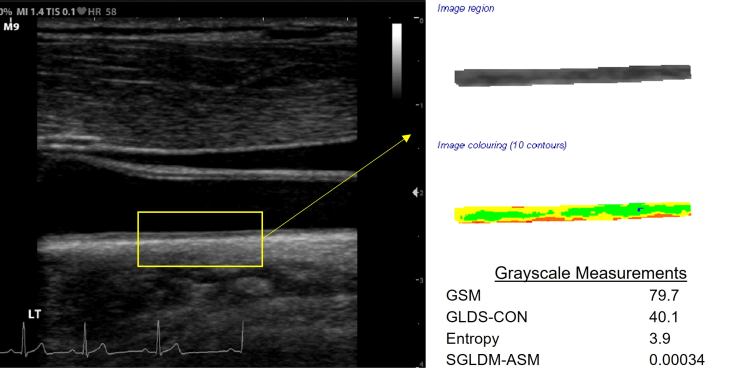

Below is a B-mode ultrasound image of the distal common carotid artery with far wall extraction, color coding of normalized and standardized grayscale values, and grayscale measurements of early arterial injury.